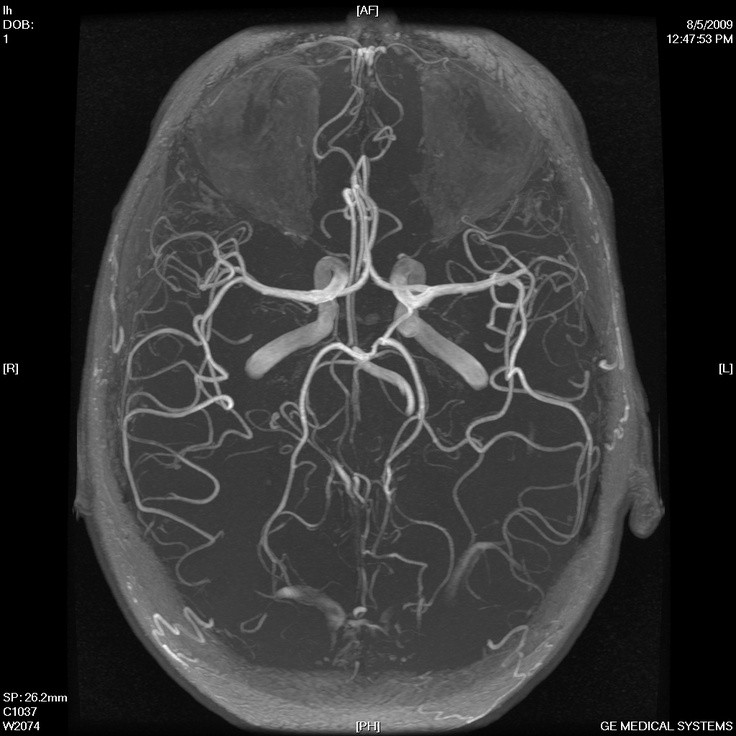

V znanstveni reviji Proceedings of the National Academy of Sciences je bila nedavno objavljena britansko-nizozemska študija, v kateri so se znanstveniki spraševali, kako se izogniti nevrološkim posledicam, ki pogosto sledijo pretresu možganov. Prvotnim znakom, kot so bruhanje, glavobol in izguba zavesti, v najbolj črnem scenariju sledijo hujše težave - otekanje možganov, možganske krvavitve, motnje vedenja in spomina ter epileptični napadi.

Pretres možganov je pogosta poškodba pri tistih, ki se ukvarjajo s kontaktnimi športi, kot sta rugby ali boks, ali pa so samo nekoliko bolj nerodni. Po močnem udarcu v glavo pride do poškodbe možganskih celic in žilic, zato se na tem mestu razvije vnetje, pri katerem glavno vlogo odigra kompleks membranskega napada. To je del prirojenega imunskega sistema, ki brez pomoči protiteles prepozna in odstrani poškodovane celice.

Raziskovalna skupina je tekom raziskave razvila protein, ki se hitro in specifično veže ravno na omenjeni kompleks membranskega napada, ki je prisoten na mestu poškodbe. Njegova količina se je po dodatku proteina v možgane mišk zmanjšala, verjetnost naknadnih nevroloških zapletov pa je upadla za kar 50 odstotkov. Ukrep je bil izveden od pol ure do štirih ur po poškodbi, kar nakazuje na potencialno rabo v urgentni medicini.